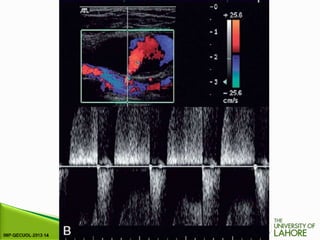

⦁ The normal waveform in the main arteries of the resting

lower limb has three components.

⦁ These represent the pressure changes which occur in the

resting lower limb arteries during the cardiac cycle.

⦁ First there is the rise in pressure and acceleration of blood

flow at the onset of systole. There is then a short period of

reversed flow as the pressure wave is reflected from the

constricted distal arterioles. This is followed by a further

period of forward flow produced by the elastic compliance of

the main arteries in diastole (Fig. 4-7A).

FIGURE 4-7 The normal femoral artery waveform. (A) In a limb at rest

three components are visible. Aliasing in the profunda artery is due to

the lower insonation angle giving a higher Doppler shift, not a focal

stenosis.

⦁ Exercise modifies this pattern by reducing the peripheral

resistance. This results in the reversed component being lost

and increased diastolic flow throughout the cardiac cycle (Fig.

4-7B). It is for this reason that ultrasound examination of the